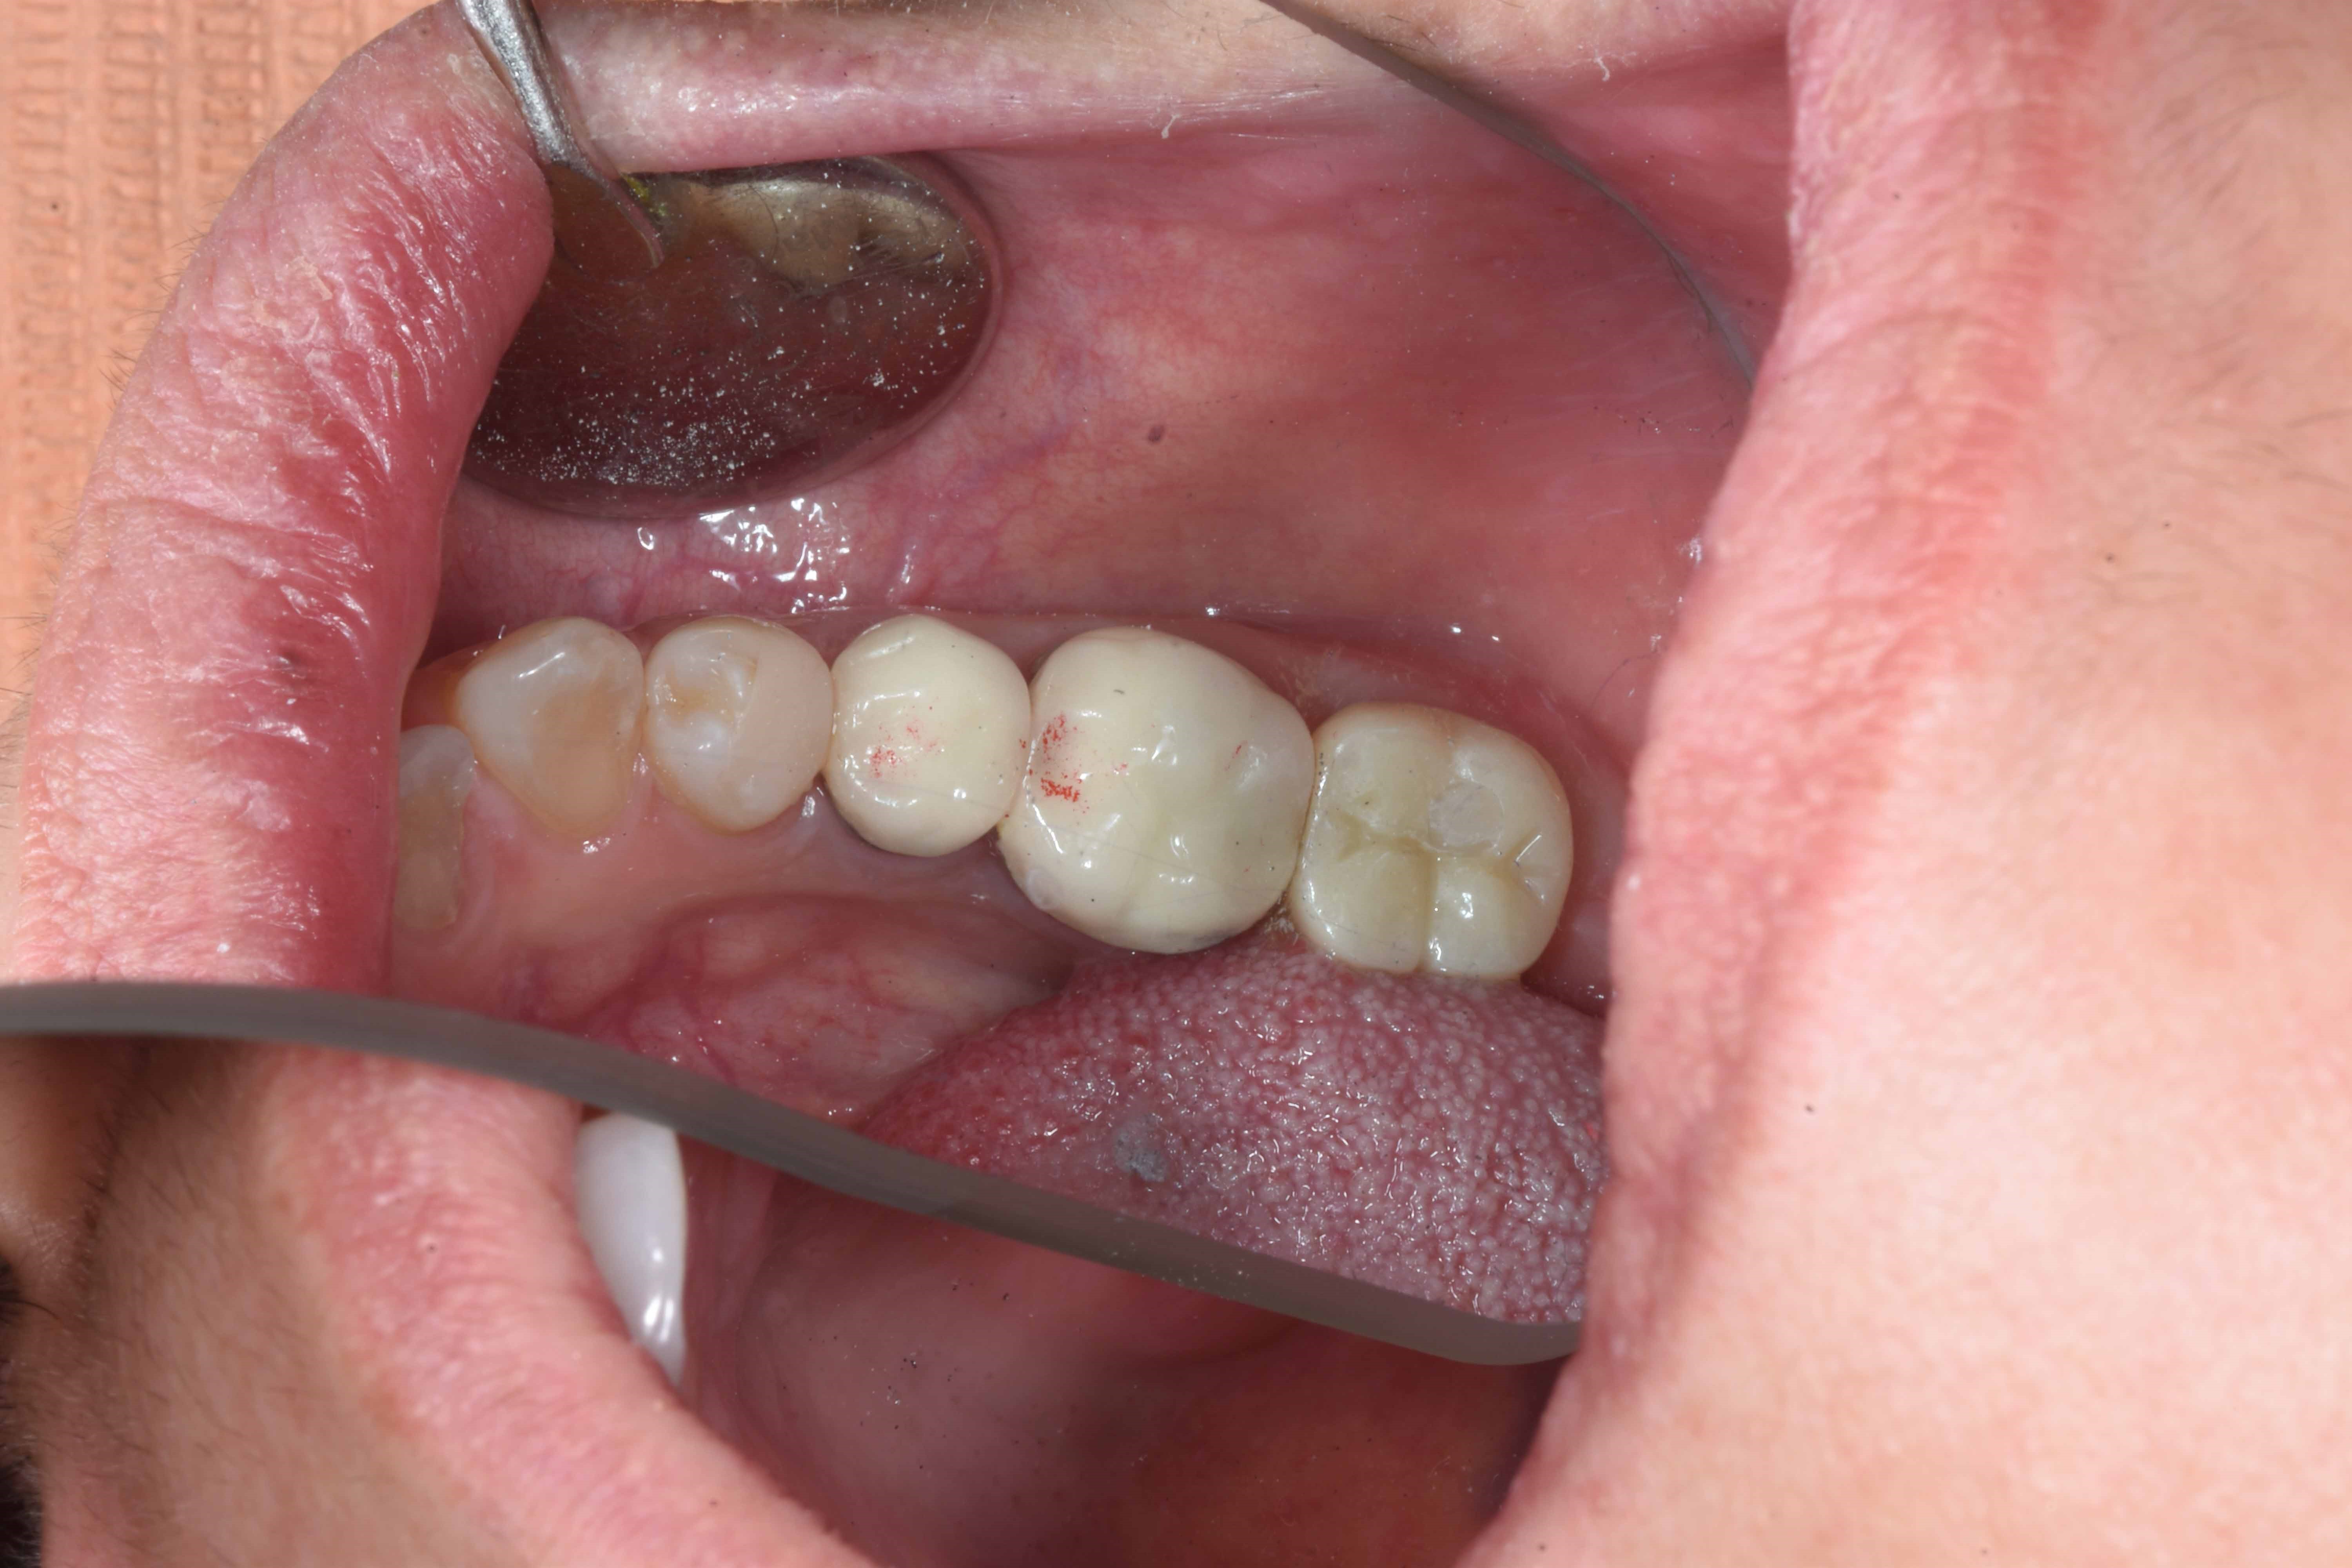

案例三

立即拔除牙根不好的牙齒

立即植入植體

鎖上癒合螺帽

2-3個月癒合,7-10天完成假牙 ,試戴、調整咬合高度並鎖上,封填,完成